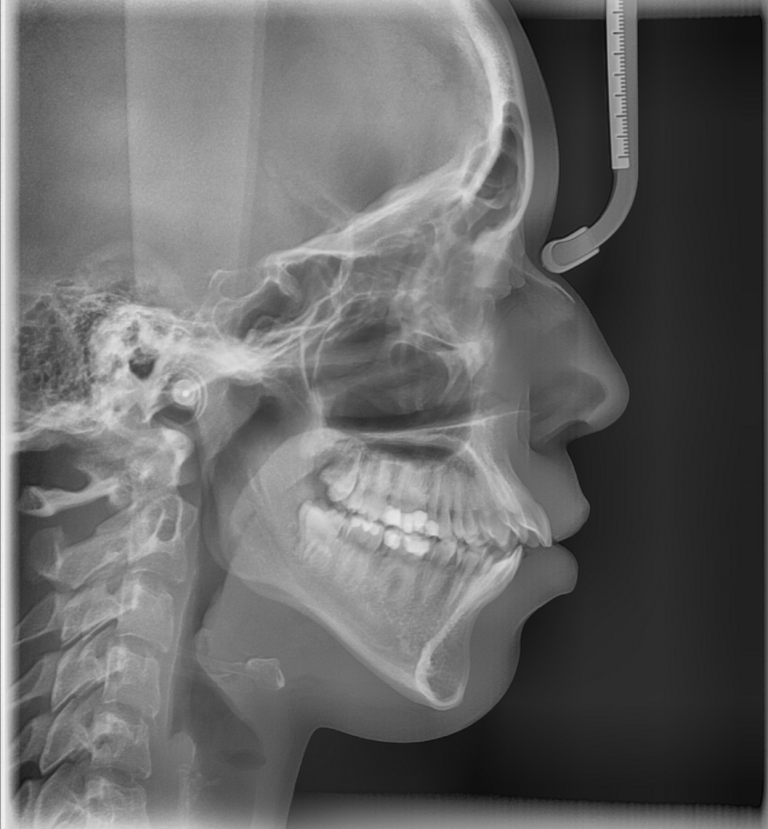

Das Fernröntgenseitenbild

Bei einer kieferorthopädischen Behandlung werden Zähne in eine neue Position verschoben. Vorher ist es wichtig zu wissen, wie die Zähne im Knochen verankert sind. Zähne dürfen immer nur so weit bewegt werden, dass noch ausreichend Knochen und ein gesunder Zahnhalteapparat vorhanden sind. Andernfalls könnte sich das Zahnfleisch zurückziehen und der Zahnhalteapparat geschädigt werden. Im schlimmsten Fall können sich Zähne lockern oder sogar verloren gehen. Weil dies auf der Panorama-Aufnahme nicht ausreichend beurteilt werden kann, ist noch ein zweites Röntgenbild, das sogenannte Fernröntgenseitenbild (FRS), nötig.

Warum ein Fernröntgenseitenbild?

Bei Kindern und Jugendlichen gibt das Bild Auskunft über die Wachstumsrichtung des Kiefers. Dieses Wissen ist entscheidend für die Planung von Therapiezeit und -art sowie die Auswahl der Zahnspange.

Anhand der seitlichen zweidimensionalen Röntgenaufnahme beurteilt dr. Anna Schroen, wie die Kiefer zueinander positioniert sind. Sie erkennt, wie die Frontzähne von der Seite aus betrachtet im Knochen stehen. Dadurch ist es möglich zu beurteilen, wie dick die Knochenschicht ist, die die Zahnwurzeln umgibt. Davon kann sie ableiten, welche Zahnverschiebungen sicher möglich sind - und vor allem, welche nicht.